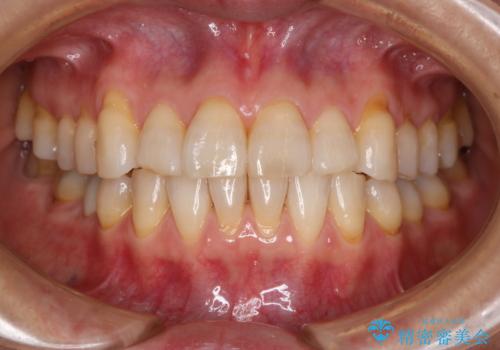

【インビザライン】前歯のがたつきを目立たない装置で治療

【インビザライン】がたつきをマウスピースできれいにしたい

【インビザライン】かみ合わせを整えたい

【非抜歯】インビザラインでガタつきと口元を改善!非抜歯でも印象が変わる矯正治療

【非抜歯】マウスピースでオープンバイトを治す

【インビザライン】すきっぱを治したい